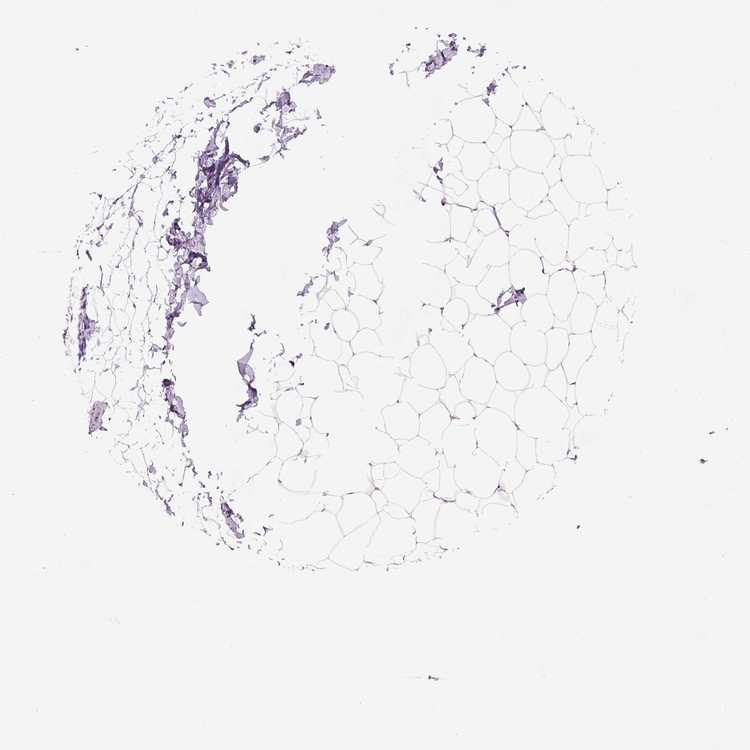

BREAST - Antibody stainingi

Antibody staining in the annotated cell types in the current human tissue is reported as not detected, low, medium, or high, based on conventional immunohistochemistry profiling in selected tissues. This score is based on the combination of the staining intensity and fraction of stained cells.

Each image is clickable and will lead to virtual microscopy that enables deeper exploration of all samples and also displays staining intensity scores, fraction scores and subcellular localization as well as patient and tissue information for each sample.

Antibody HPA071114

Adipocytes Not detected

Glandular cells Not detected

Myoepithelial cells Not detected